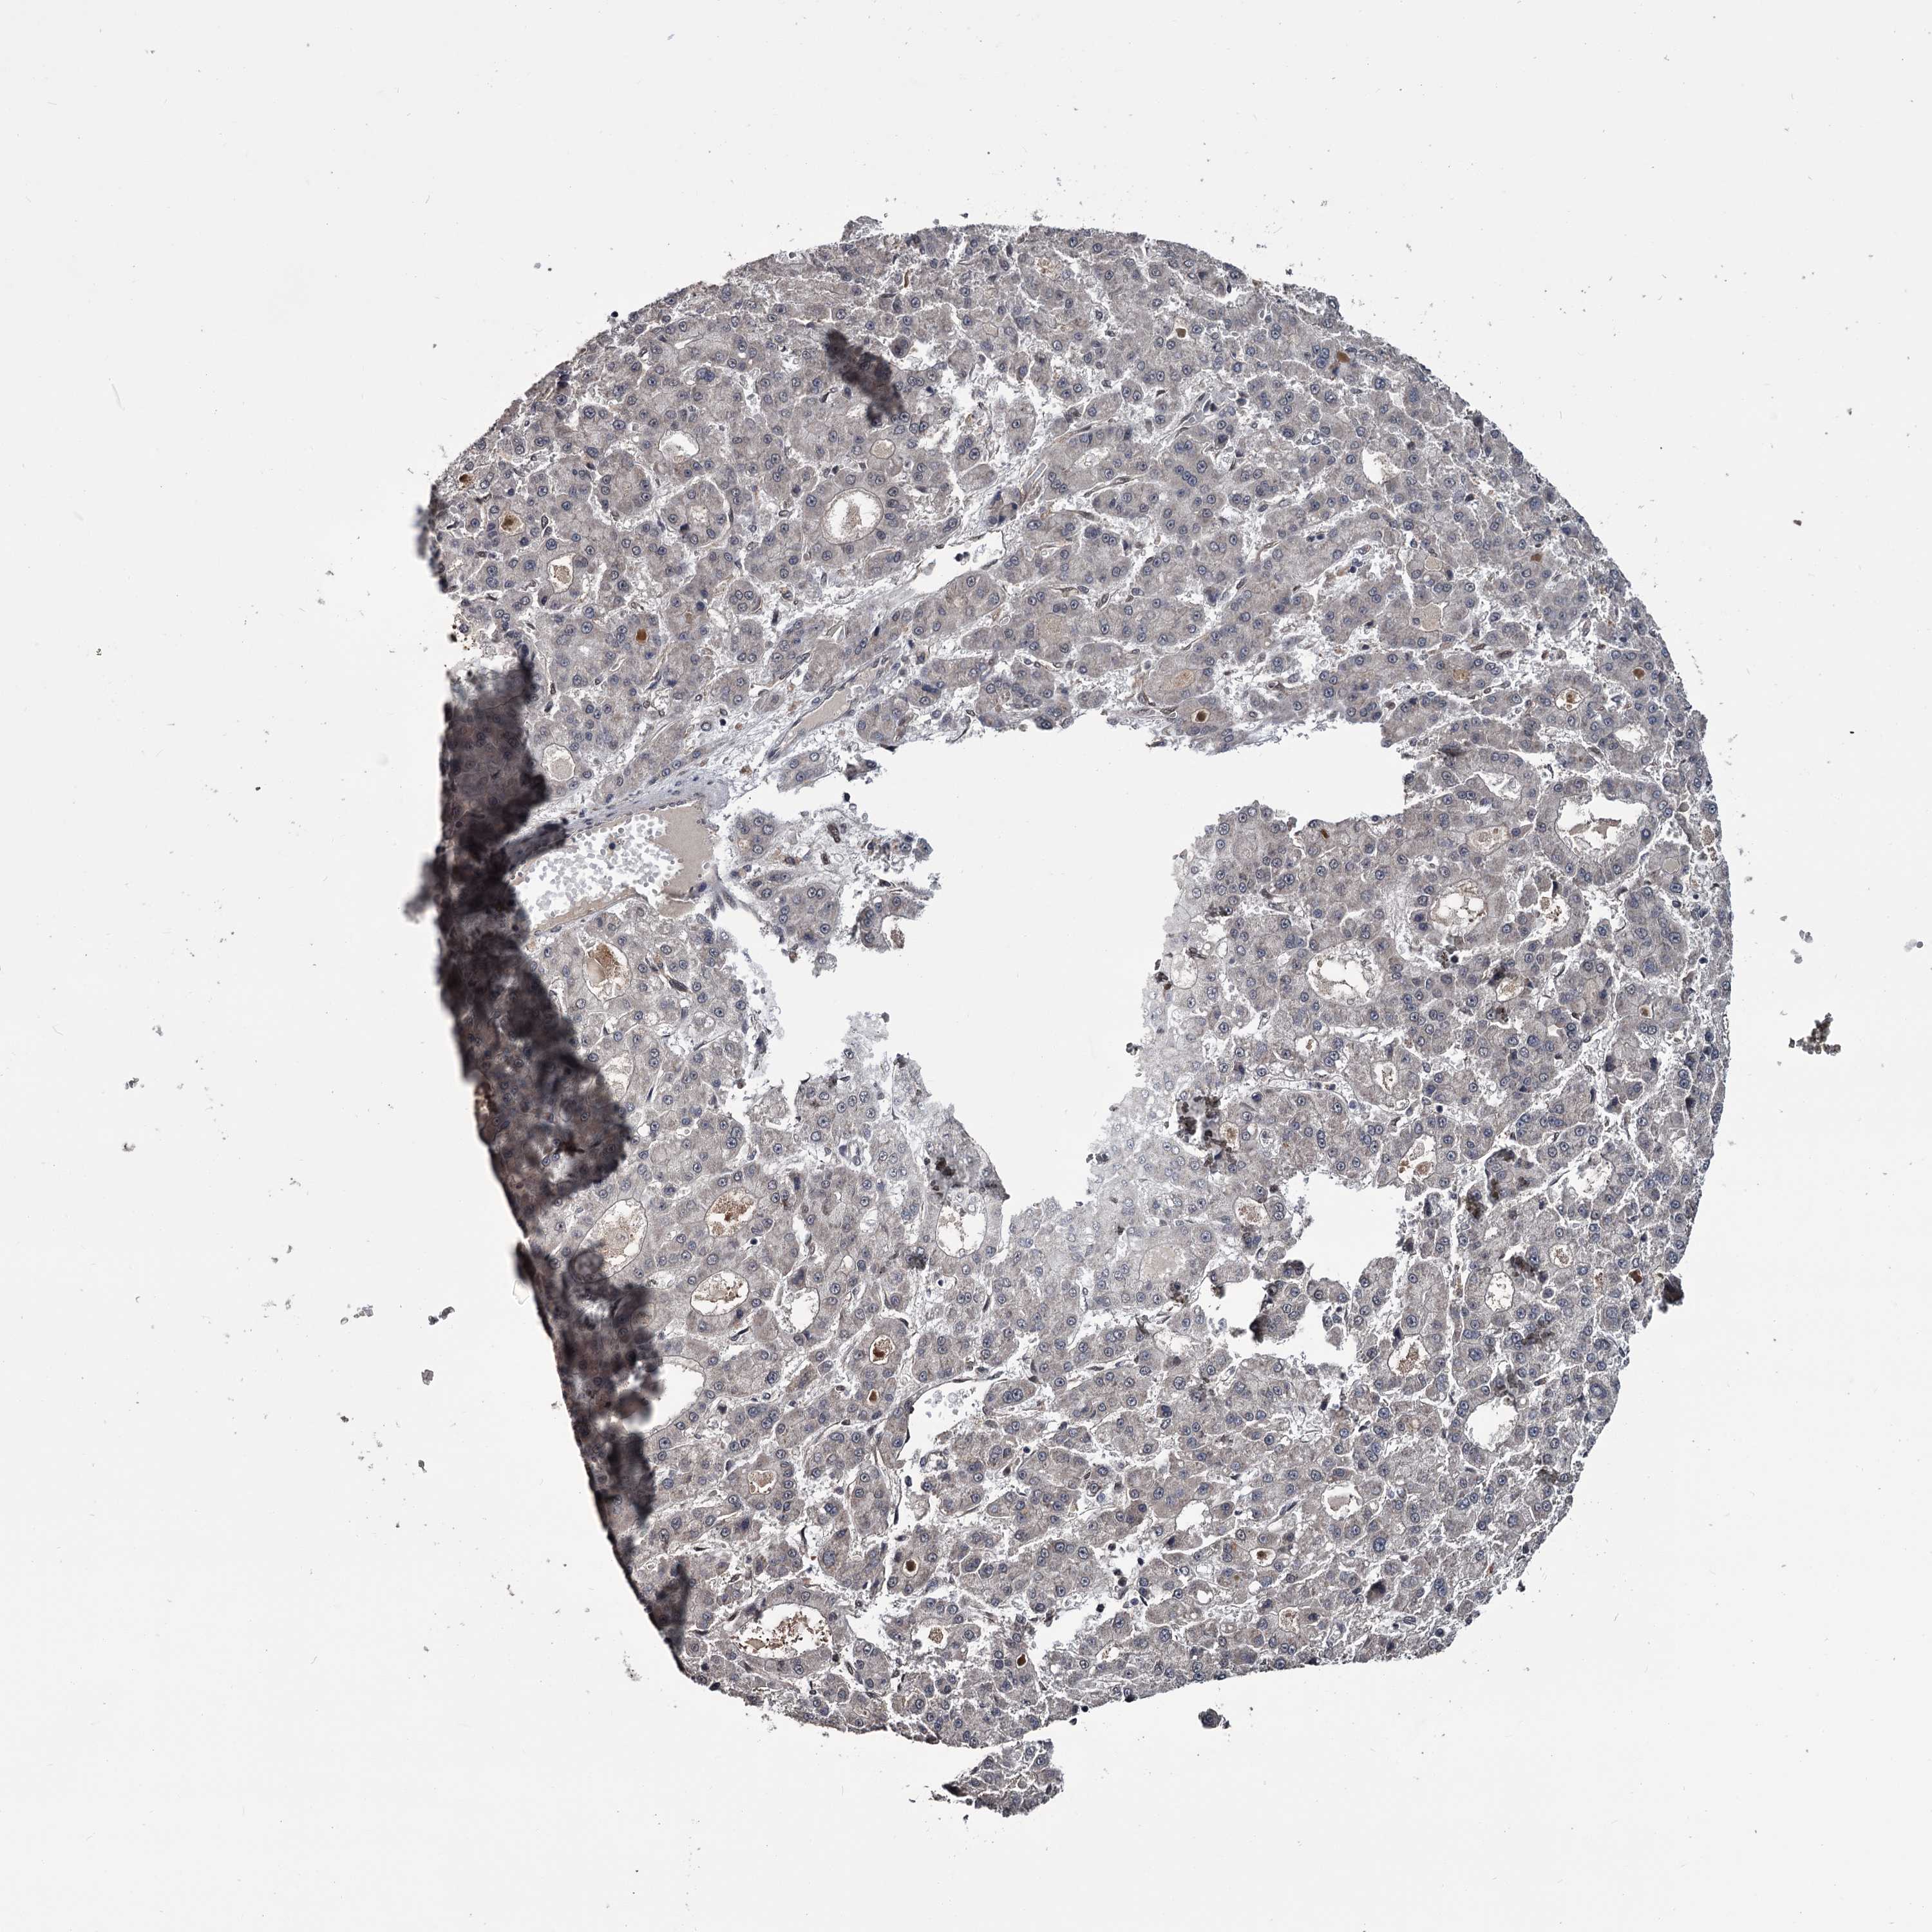

LIVER CANCER - Protein expressioni

A mouse-over function shows sample information and annotation data. Click on an image to view it in a full screen mode. Samples can be filtered based on level of antibody staining by selecting one or several of the following categories: high, medium, low and not detected. The assay and annotation is described here.

Note that samples used for immunohistochemistry by the Human Protein Atlas do not correspond to samples in the TCGA dataset.

Antibody stainingi

Antibody staining in the annotated cell types in the current human tissue is reported as not detected, low, medium, or high, based on conventional immunohistochemistry profiling in selected tissues. This score is based on the combination of the staining intensity and fraction of stained cells.

Each image is clickable and will lead to virtual microscopy that enables deeper exploration of all samples and also displays staining intensity scores, fraction scores and subcellular localization as well as patient and tissue information for each sample.

Antibody HPA038562

Staining

High

Medium

Low

Not detected

Intensity

Strong

Moderate

Weak

Negative

Quantity

>75%

75%-25%

<25%

None

Location

Nuclear

Cytoplasmic/membranous

Cytoplasmic/membranous,nuclear

Cholangiocarcinoma

Carcinoma, Hepatocellular, NOS